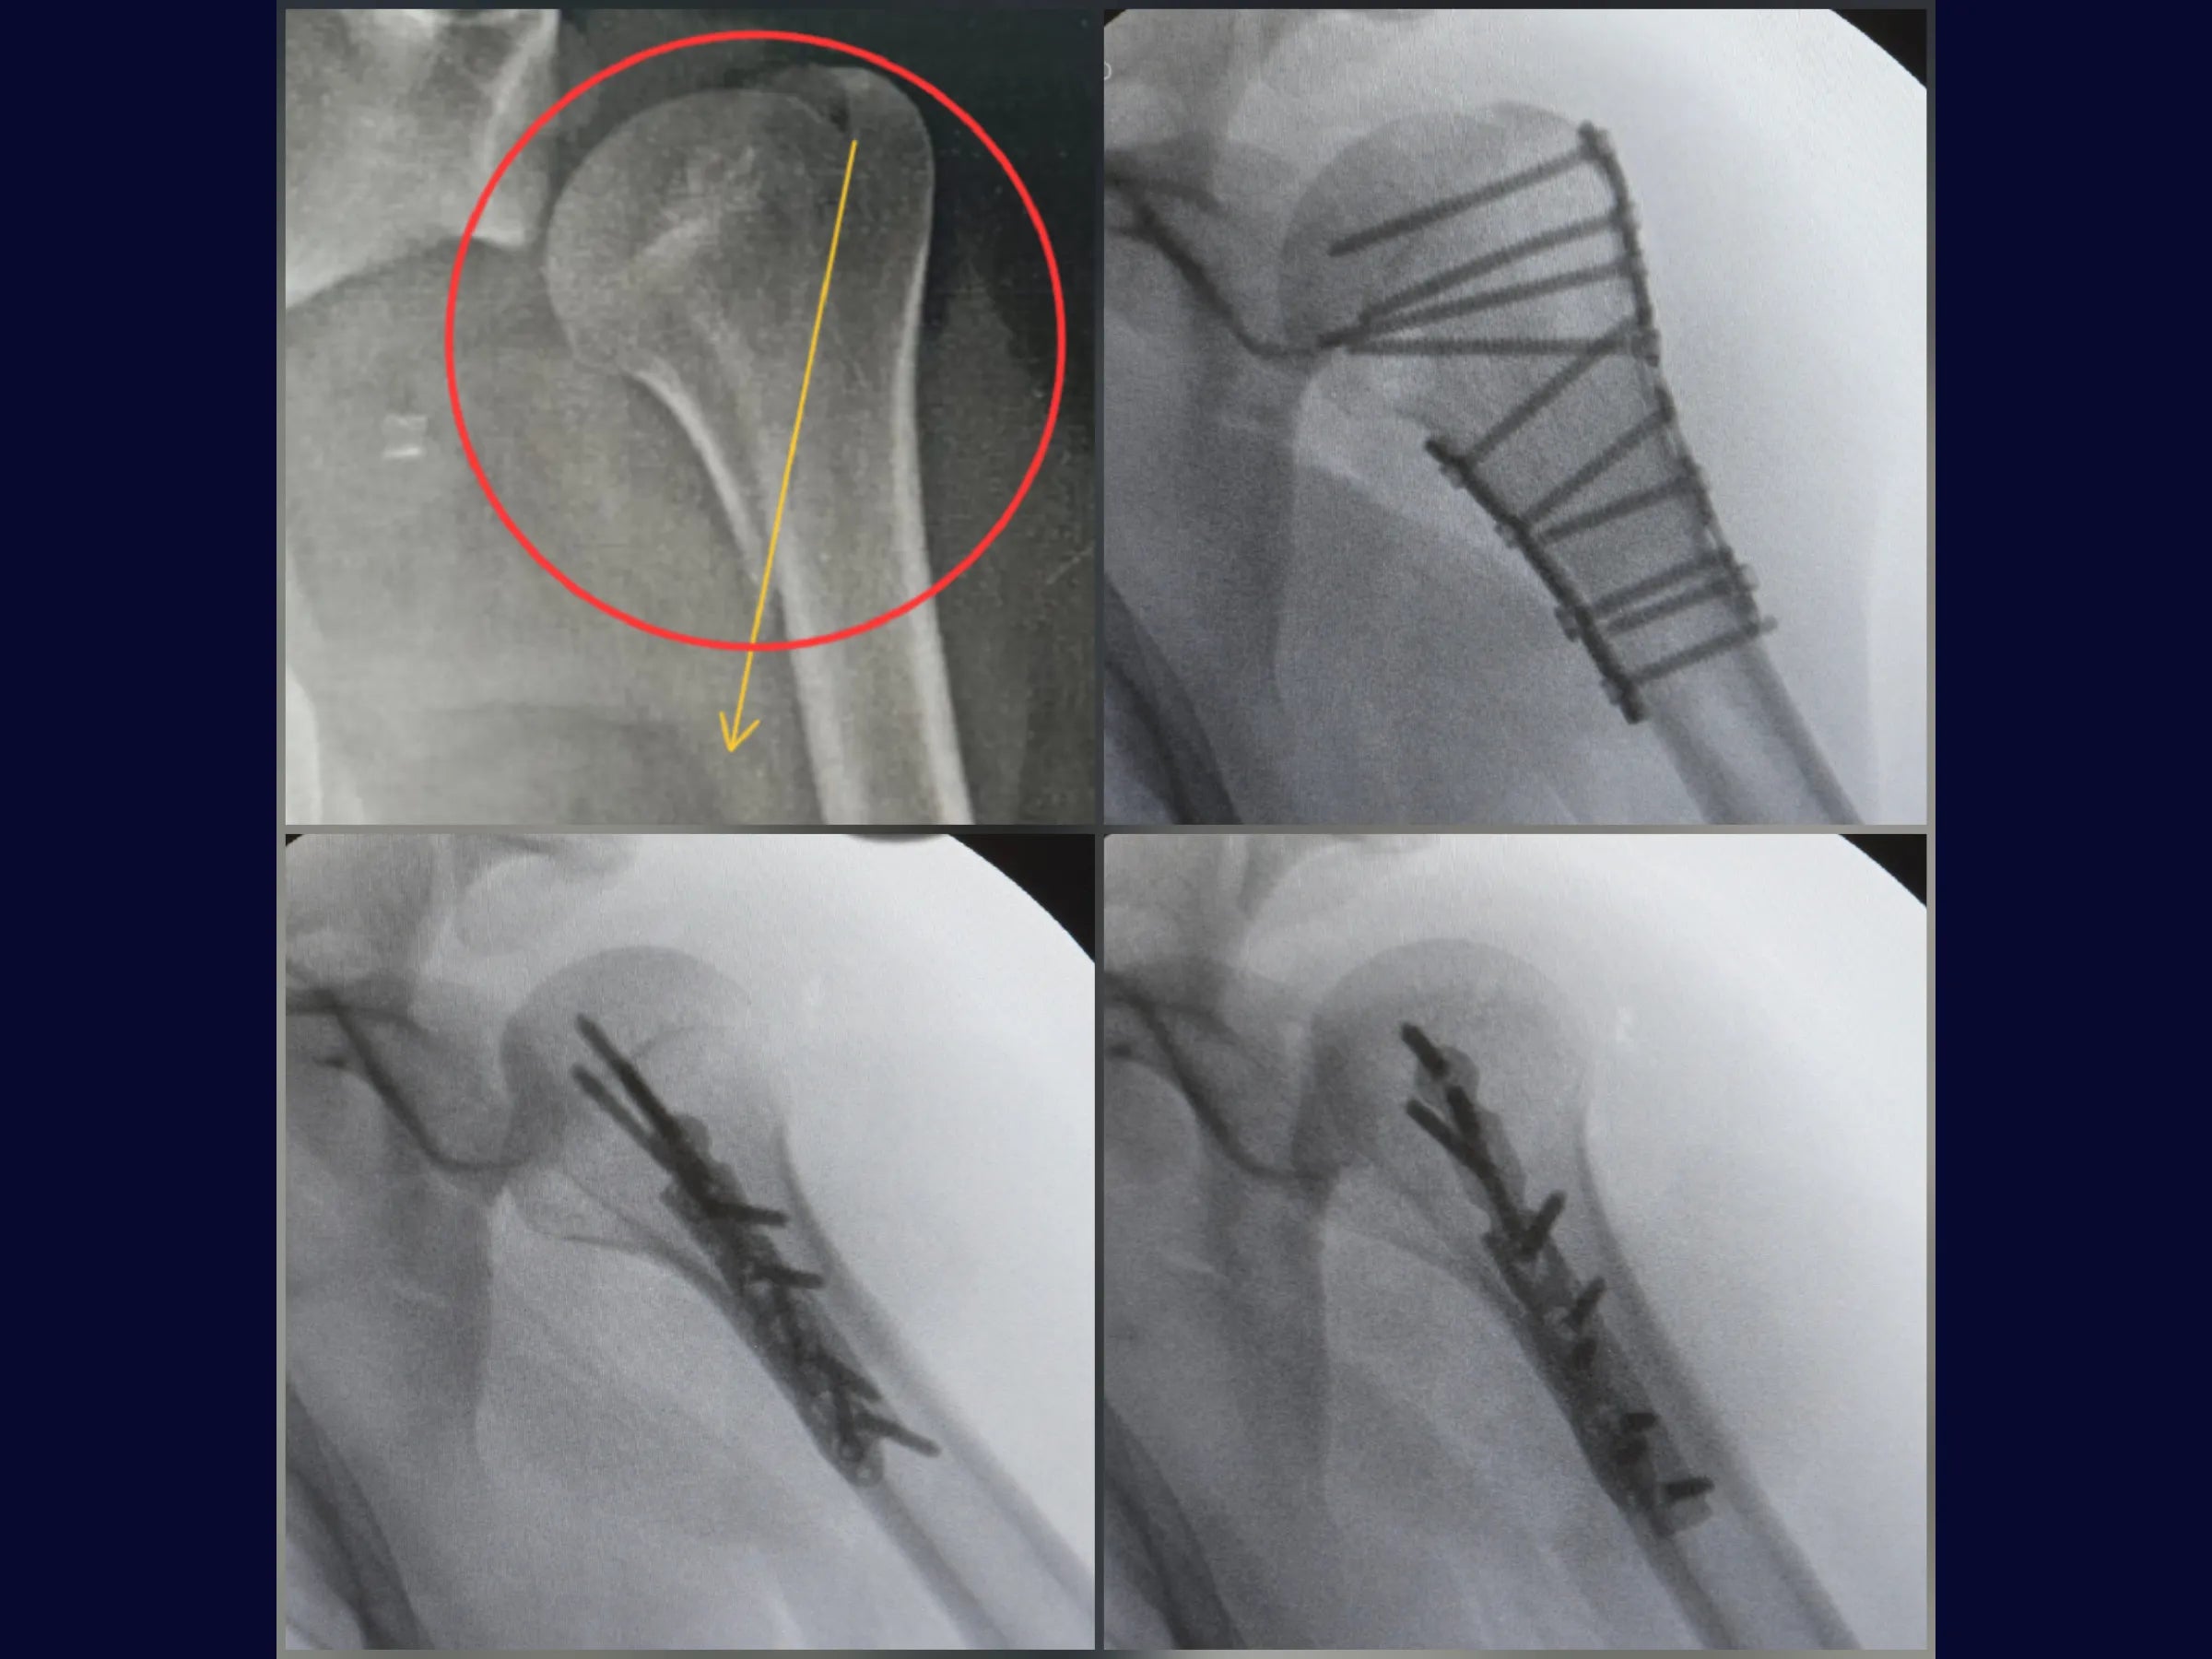

A consolidação parcial em fraturas proximais do úmero com cisalhamento medial representa um desafio frequente na prática ortopédica, dificultando a redução anatômica e a estabilização adequada.

Este treinamento apresenta, em alta definição e sob a perspectiva do cirurgião, a aplicação da placa medial anti-cisalhante associada à placa lateral de baixo perfil, demonstrando passo a passo a redução indireta, a preservação das estruturas anatômicas e a estabilização biomecânica da fratura.

- Redução indireta de fratura proximal do úmero com cisalhamento medial.

- Fixação combinada: placa medial anti-cisalhante + placa lateral de baixo perfil.

- Redução Indireta com Placa: Uso da própria placa como alavanca para superar consolidação parcial e restaurar a altura da cabeça umeral.

- Estabilidade Biomecânica Avançada: Combinação de placa medial anti-cisalhante com placa lateral → resistência contra cisalhamento e rotação.